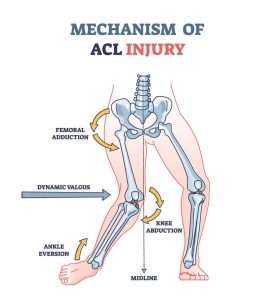

مکانیزم آسیب پارگی ACL